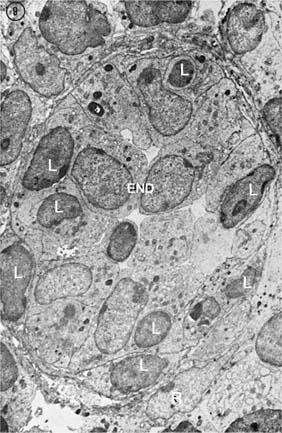

Figure 14.15. A postcapillary venule is practically occluded by the tall endothelial cells (End). Some lymphocytes (L) are crossing the wall of the high endothelial venule and enter the lymph node. The wall is surrounded by reticular cells (R) (×4,500). (From Clark SJL Jr. The reticulum of lymph nodes in mice studied with the electron microscope. Am J Anat 1962;110:217, with permission.)